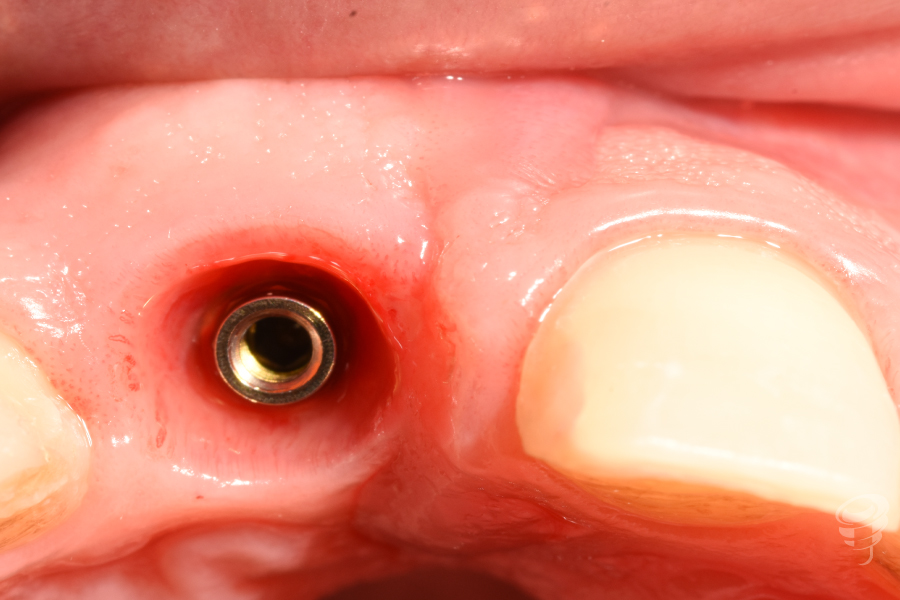

Fase 2: Controles y Segunda Etapa (Mes 4)

- Confirmación de osteointegración (ISQ > 70).

- Impresión convencional para realizar un encerado diagnóstico estético y posteriormente una realización de réplica del perfil de emergencia con la técnica de Hinds, para solapar una medida convencional con una digital (escáner intraoral).